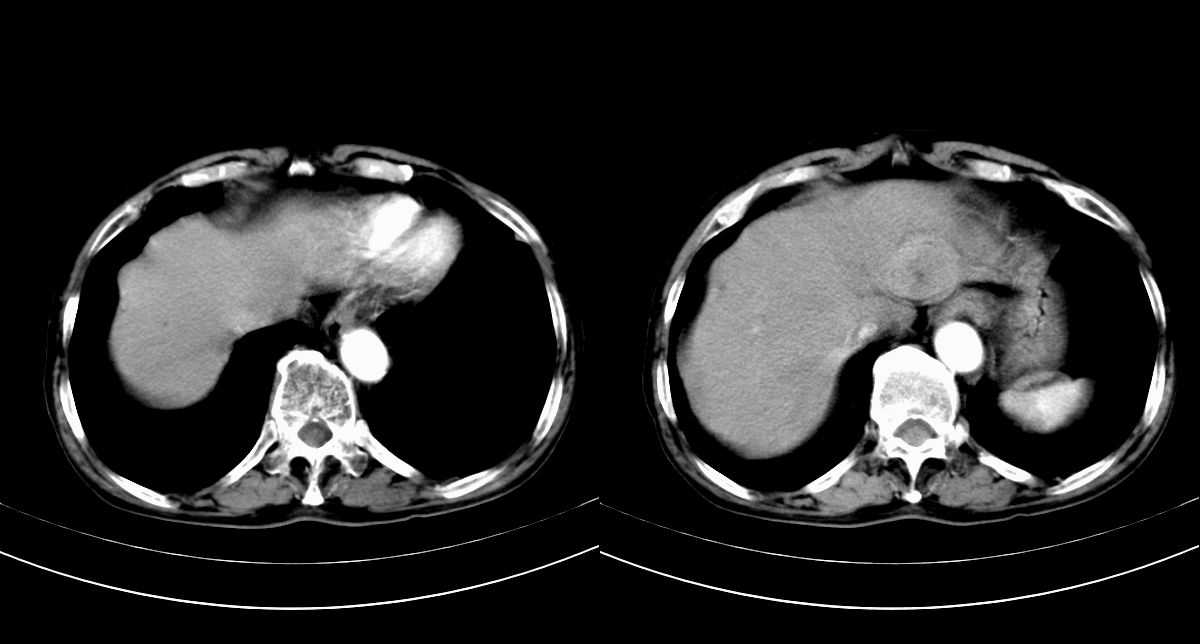

男,79y,无不适。体检发现肝脏占位。

肝内多发低密度结节,增强动脉期明显强化,门脉期逐渐下降,内有液化坏死区。

诊断:

肝细胞癌(结节型)

鉴别:肝转移癌。

肝内多发低密度结节灶,增强动脉期明显不规则环状强化,;门脉期逐渐下降,肿瘤壁厚薄不一,内有坏死液化区。

诊断:肝转移癌可能

鉴别:1原发性肝癌(强化方式符合,建议查afp)

2肝脓肿(无临床病史支持)